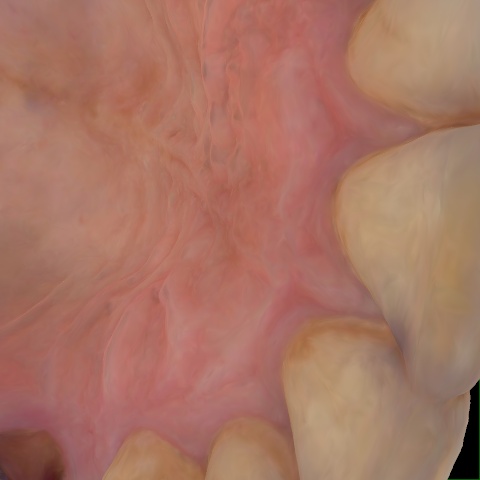

Annotated as "Good"